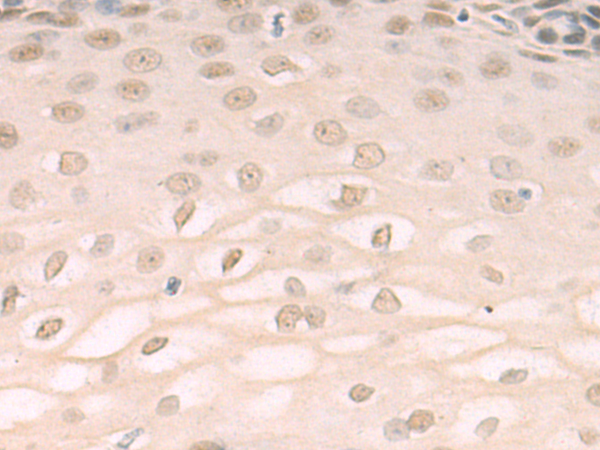

分类: 科研抗体货号: P10666别名: ADTG; CLAPG1应用: IHC反应种属: Human, Mouse